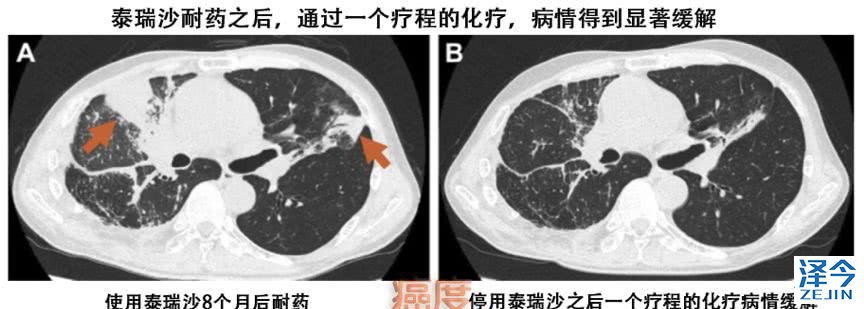

本案例中的这位患者在初步耐药后立刻转换了方案,选择了培美曲塞+卡铂+贝伐珠单抗进行化疗,结果证明化疗效果很好,如上图所示,一个疗程就见到了效果。